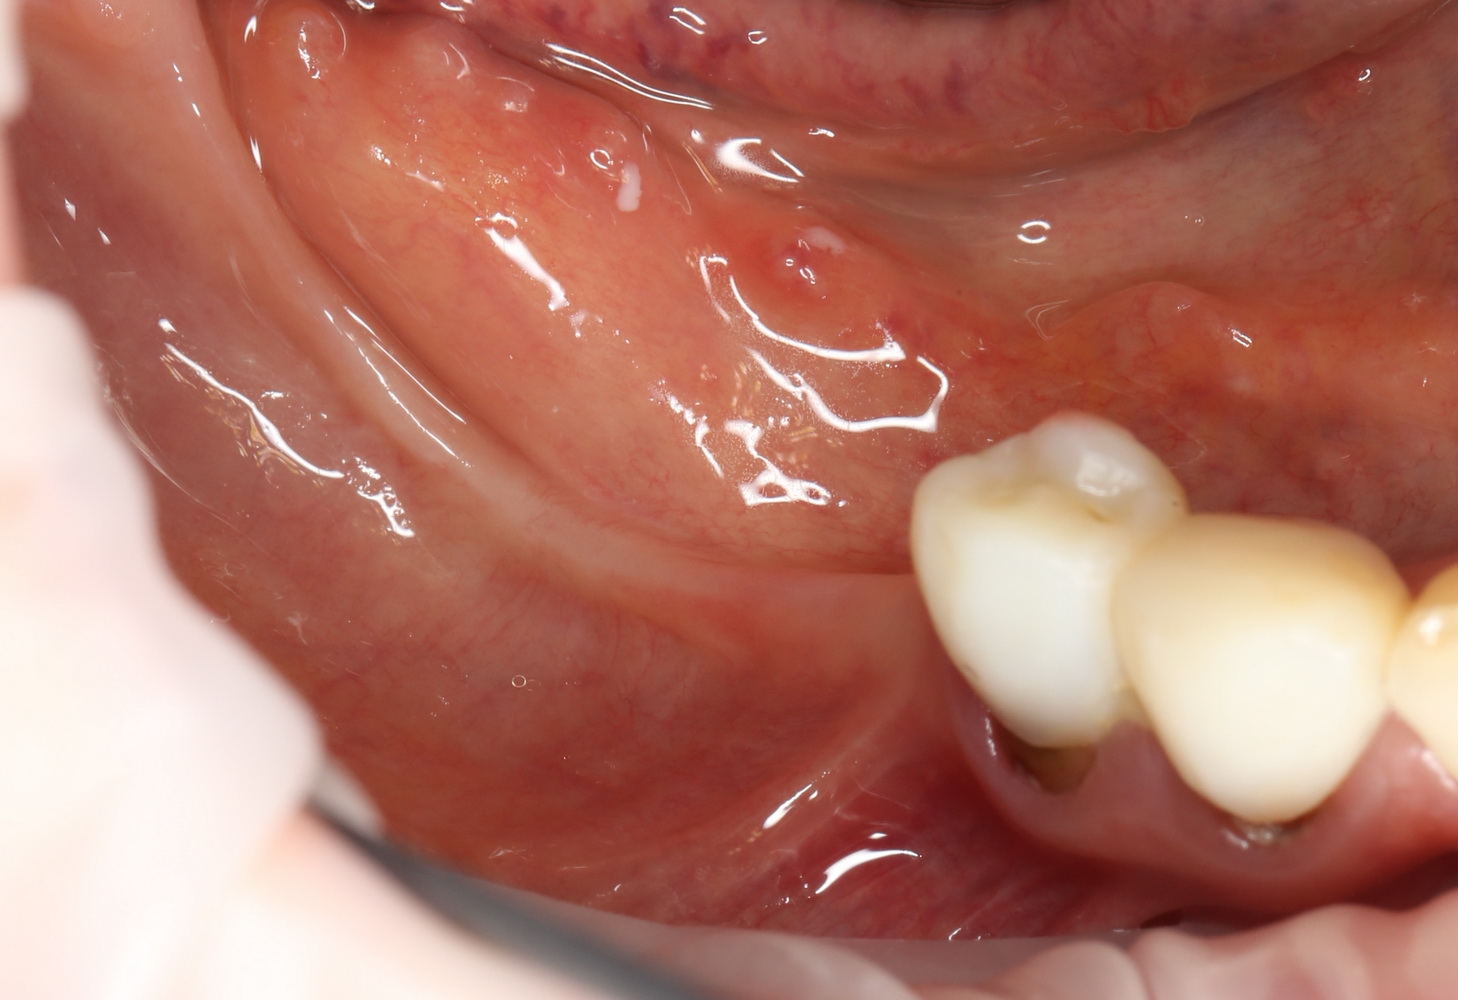

Через 3 месяца мы готовы приступить к формированию десны. И каким-то невероятным образом, у нас получился даже избыток слизистой оболочки. Что, безусловно, очень даже хорошо:

По фотографии хорошо видно, как изменилась форма альвеолярного гребня после операции.

Наша пациентка это знает, поэтому через год заглянула к нам в клинику. И вот, что мы увидели:

На мой взгляд, это — уже хоть какой-то результат лечения. И, по мнению пациентки, с поставленной задачей мы справились.